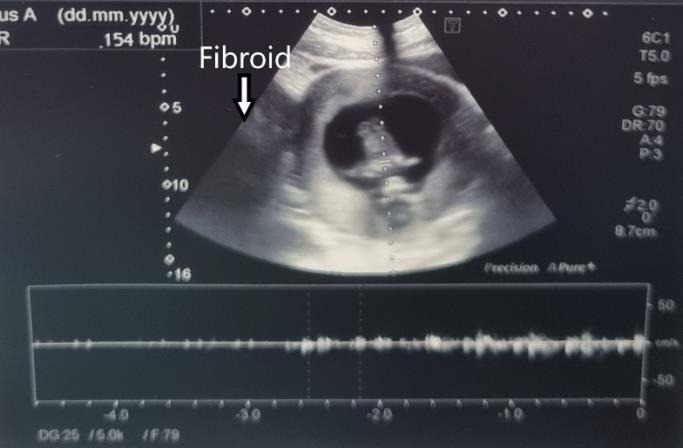

The management of symptomatic uterine fibroids during pregnancy is a challenging situation. In some cases, surgical therapy can be required. Reports indicate that both laparotomy and laparoscopy are safe methods. However, laparoscopy is associated with less morbidity. This paper describes the case of a 31-year-old woman with a symptomatic uterine fibroid which was removed by gasless laparoscopy.

Abstract Image